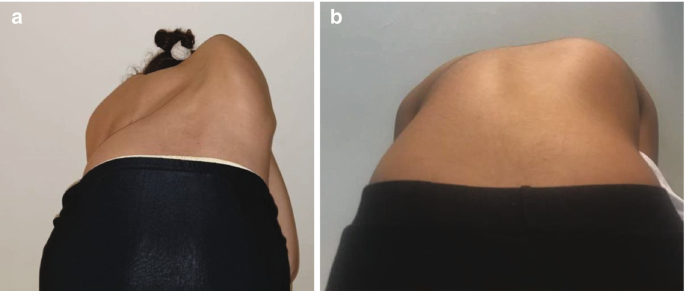

2. بروز في أحد جانبي الظهر

عند انحناء الطفل للأمام، قد يظهر بروز في جهة واحدة من الظهر، وهو من العلامات المهمة التي تستدعي الانتباه.

4. اختلاف شكل الخصر أو القفص الصدري

اختلاف مستوى الخصر أو بروز أحد الجانبين أكثر من الآخر يشير إلى عدم التوازن العضلي أو وجود اعوجاج.

- اجعله ينحني للأمام ببطء.

- راقب الظهر من الخلف.

- بروز في جهة واحدة

- عدم تماثل واضح

- اختلاف مستوى الجانبين

- ظهور بروز في جهة واحدة